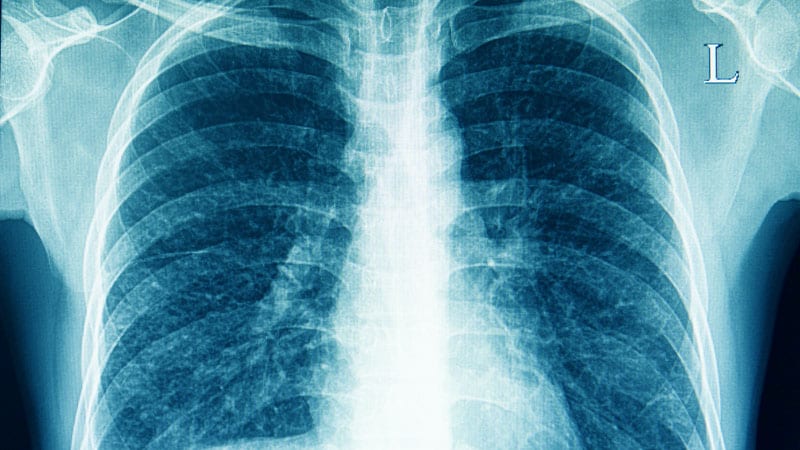

Рентген здоровых легких: примеры снимков и советы

Раздел: Сокровищница опыта